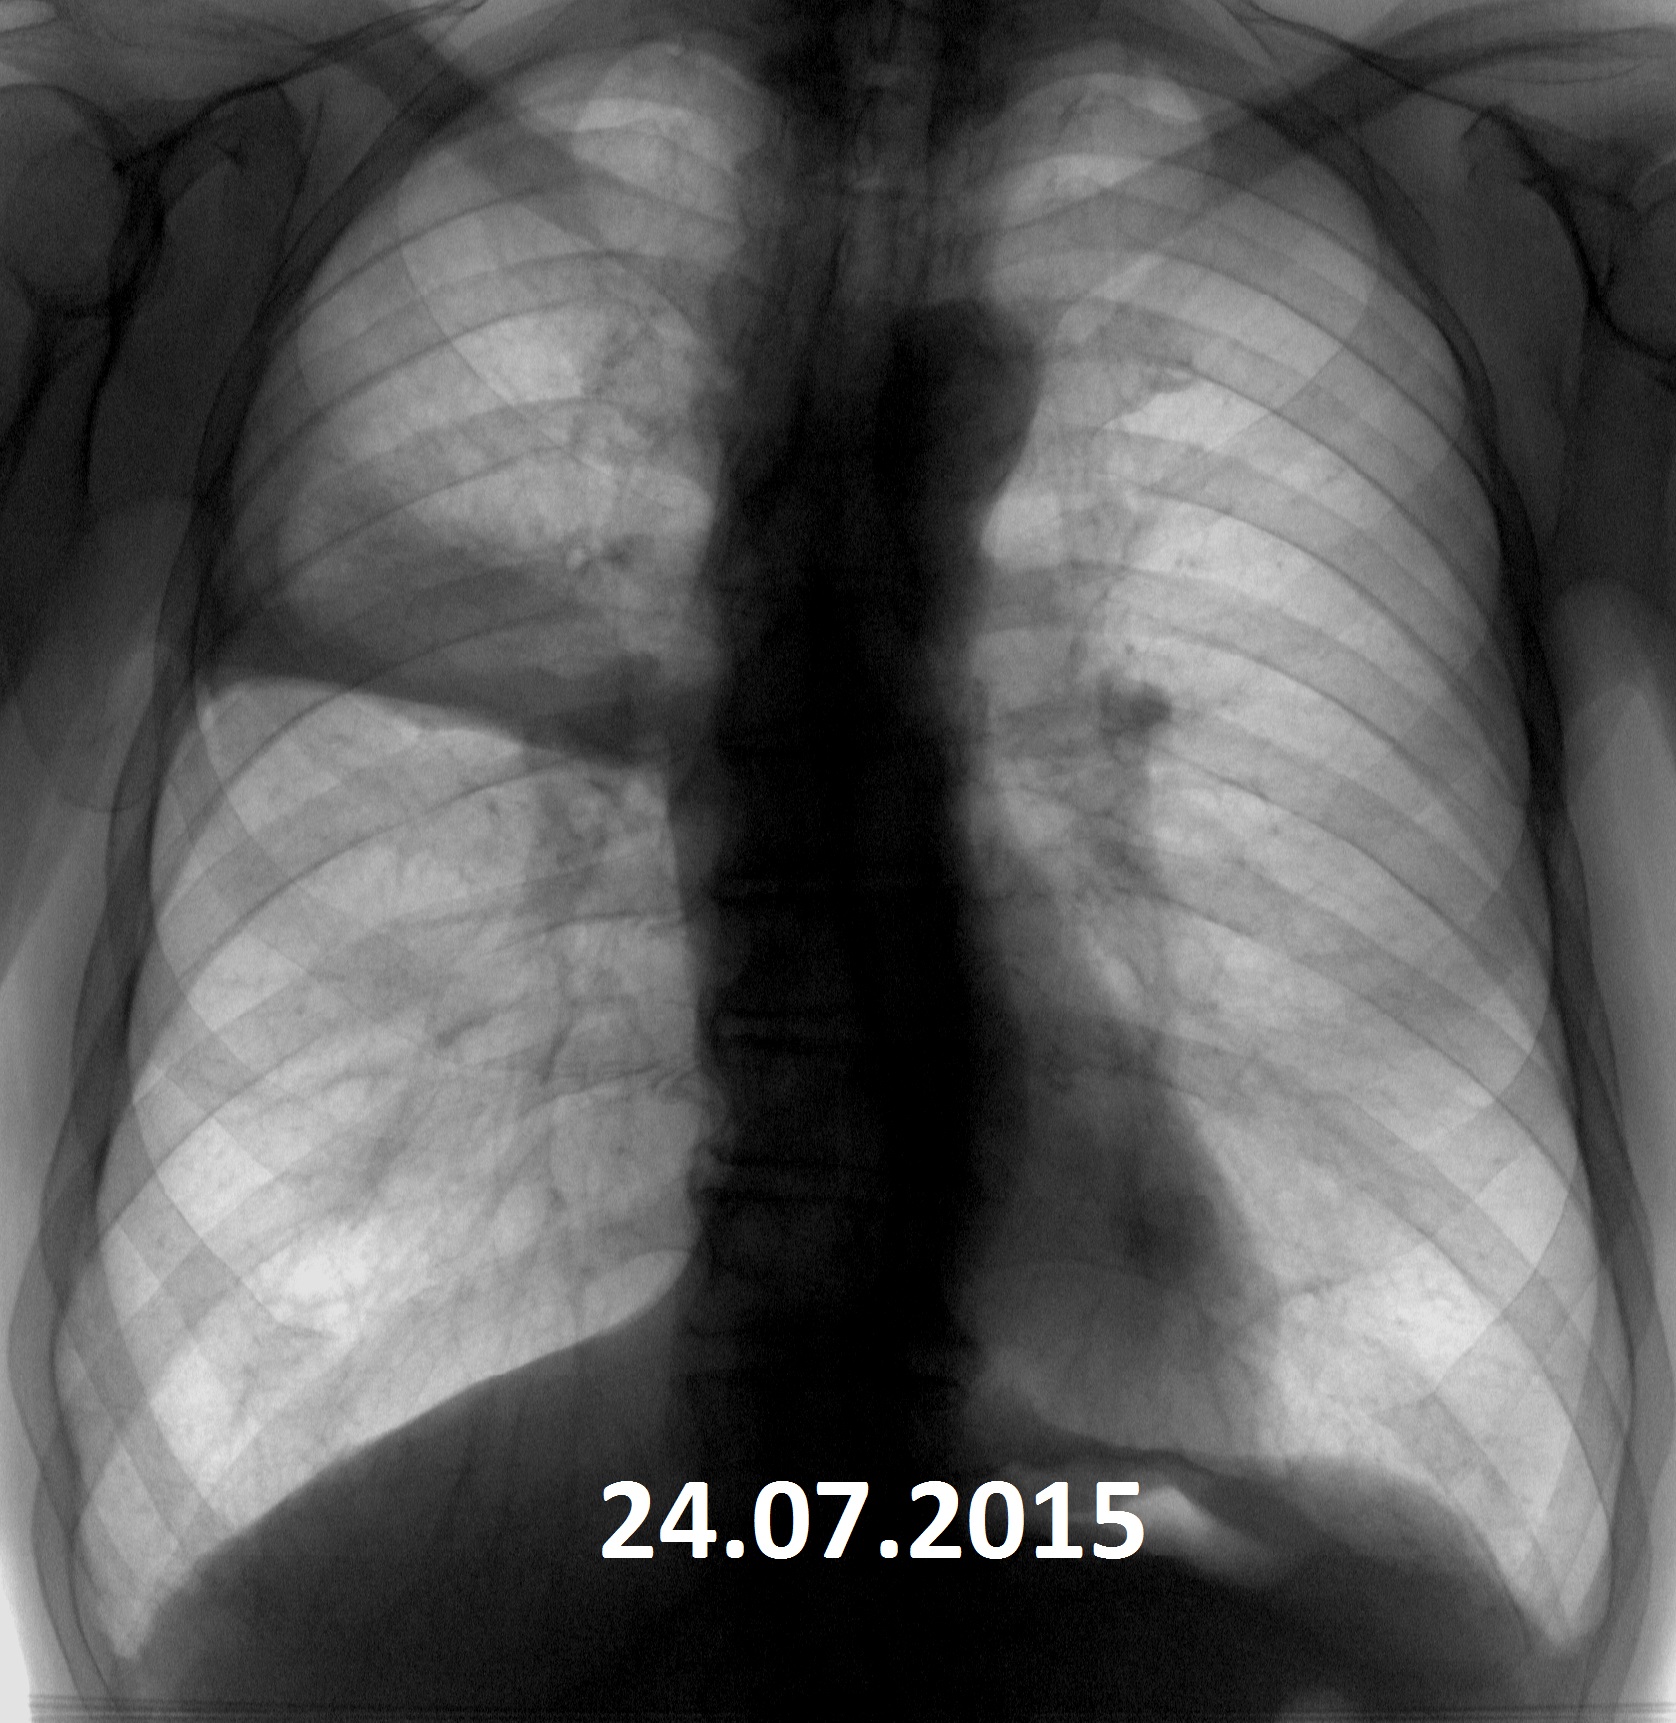

Рентген здоровых легких: примеры снимков и советы

Раздел: Сокровищница опыта